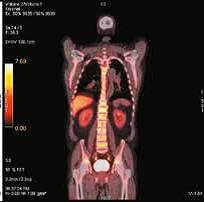

121031100301-1. «Прогнозирование эффективности специфической терапии с помощью позитронной эмиссионной томографии с 3′-дезокси-3′-[18F]фтор-л-тимидин при миелоидных новообразованиях». Выявлено, что степень захвата 18F-ФЛТ коррелирует с объемом опухолевой массы и пролиферативной активностью злокачественных гемопоэтических клеток. Так, при острых миелоидных лейкозах (ОМЛ) активный захват 18F-ФЛТ в костном мозге был выявлен в дебюте болезни, при его рецидиве или рефрактерном течении. Все параметры ПЭТ-КТ 18F-ФЛТ были сопоставлены с показателями захвата тимидина у пациента без онкологической патологии. При хронических миелоидных новообразованиях активность тимидина в костном мозге была существенно выше у пациентов с трансформацией в бластный криз. У последних этот показатель был сравним с уровнем захвата тимидина у пациентов с ОМЛ. На данном этапе продолжается анализ показателей для выявления роли исследования в оценке пролиферативной активности печени и селезенки при хронических миелоидных новообразованиях.

| ПЭТ-КТ с 18F-ФЛТ в норме с физиологическим накоплением РФП в печени и КМ | |